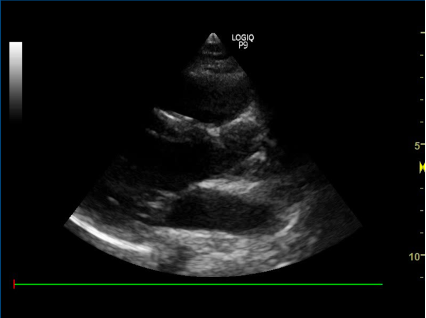

5) Apikalt 4-kammer billede:

- Nævn strukturerne:

A

proben skal pege mod patientens ve. side